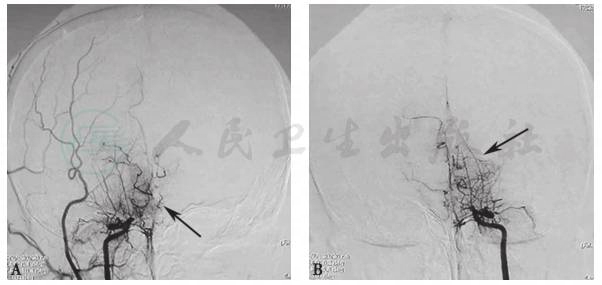

颈动脉CT示双侧颈动脉重度狭窄,颅内椎体动脉侧支循环大量形成;头颅磁共振示蛛网膜下腔出血(图2);检眼镜示左眼视网膜中央静脉阻塞;荧光素眼底造影术(FFA)示视神经萎缩;数字减影血管造影(DSA)示双侧颈内动脉远端大脑中动脉和大脑前动脉近端闭塞,代之以烟雾状细小血管(图3),双侧颈总动脉及颈外动脉通畅。

图3 数字减影血管造影(DSA)示烟雾病血管改变

黑色箭头指示左右颈内动脉远端大脑中动脉和大脑前动脉近端闭塞,代之以烟雾状细小血管